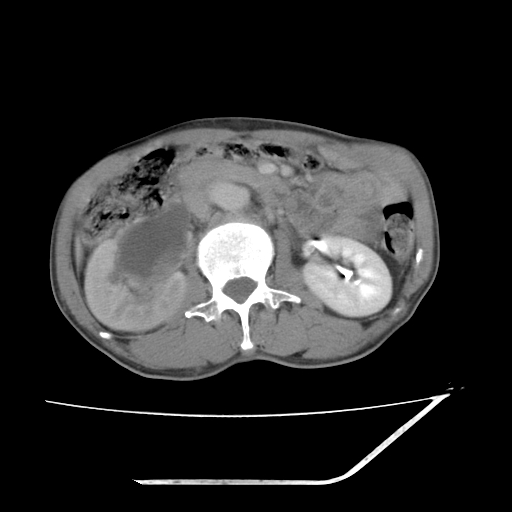

平扫

考虑右肾盂癌,肾动脉受侵,右肾功能减退,右肾盂输尿管积水,管壁增厚,考虑种植转移,应该把下面扫完的

支持右侧肾盂癌伴肾静脉瘤栓形成可能性大,右肾结石.肝右叶后段低密度影,不除外转移.

右肾盂旁ca并肾静脉瘤栓形成/肾功能降低。

右肾结石。

右肾盂癌,肾动脉受侵,右肾盂输尿管积水,管壁增厚,考虑种植转移

支持 右侧肾盂癌伴肾静脉瘤栓形成可能性大,右肾结石;肝右叶后段低密度影,不除外转移。

1.右侧肾盂癌伴肾盂积水。

2.肾脏功能减退,原因有:(1)肾动脉受侵。(2)肾静脉受侵(3)肾积水,等。本例,肾动脉显影较好,但受压明显;肾静脉无明显显示,受压或静脉癌栓,下腔静脉腔内未见明显充盈缺损。

3.右侧上段输尿管扩张,原因:(1)积水所致;(2)种植。